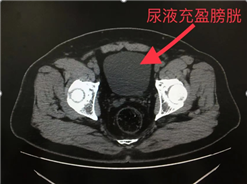

(三)憋尿:给膀胱“拍高清照”的关键一步

膀胱就像一个弹性气球,没尿的时候皱缩成一团,壁上的小病变很难发现。憋尿让膀胱充盈到乒乓球大小,医生才能清晰观察膀胱壁是否有增厚、肿块等异常。